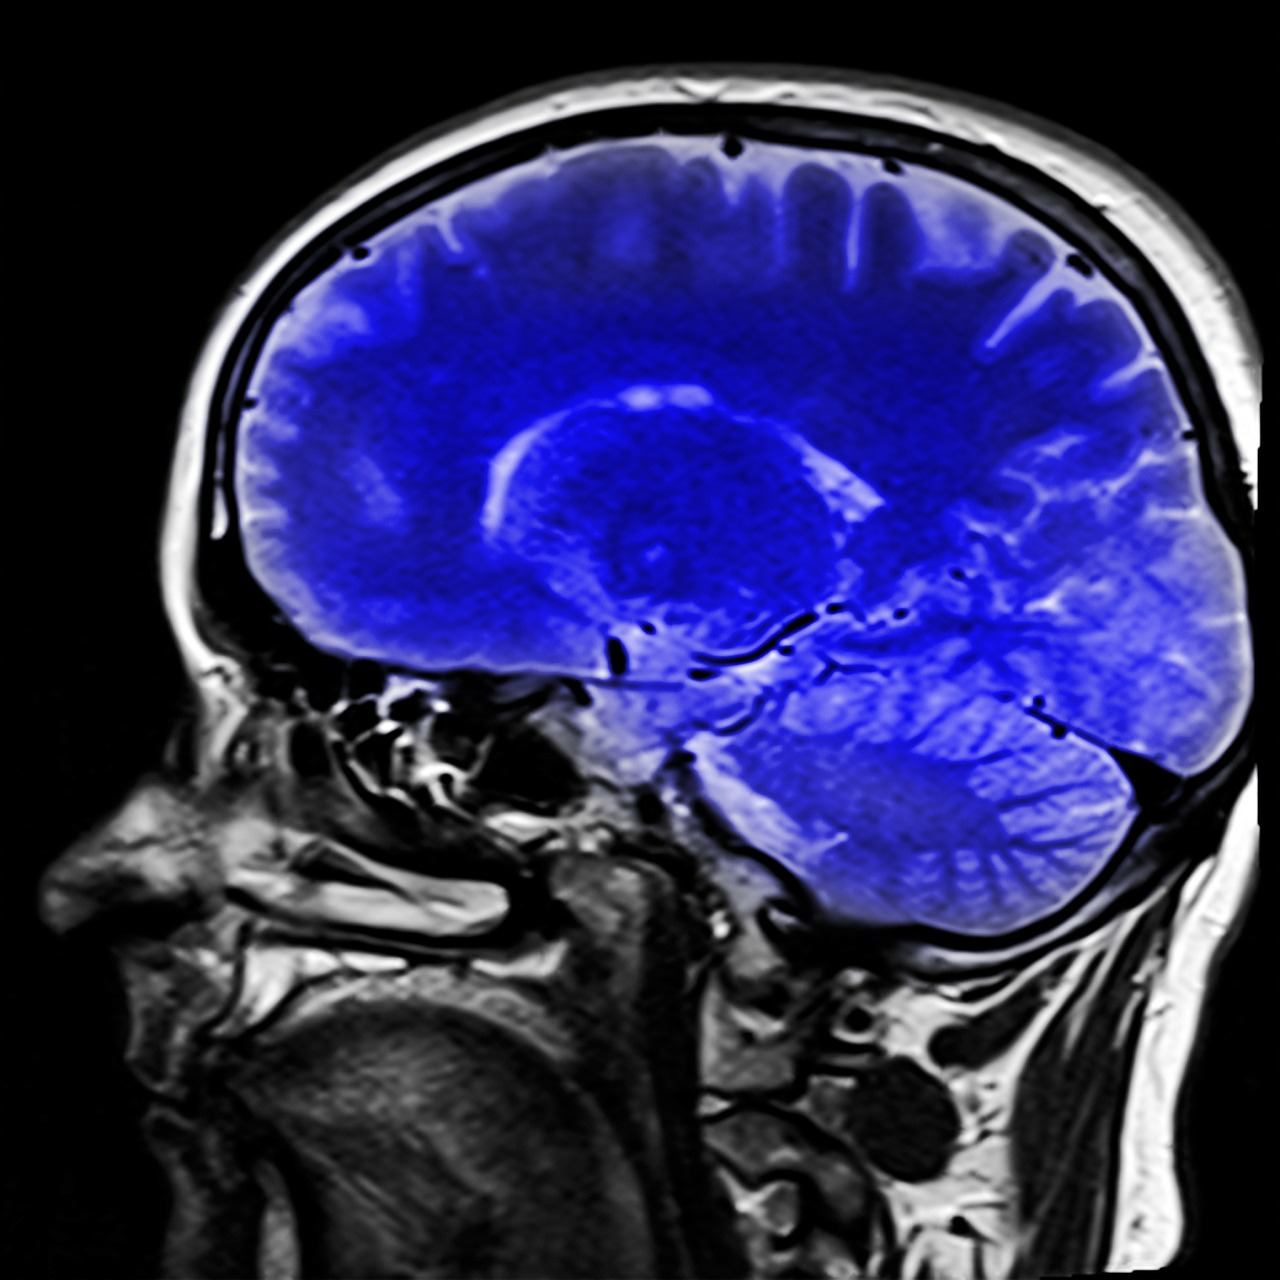

Recurrent GBM brain tumors with few mutations respond best to immunotherapy

Glioblastoma brain tumors are especially perplexing. Inevitably lethal, the tumors occasionally respond to new immunotherapies after they’ve grown back, enabling up to 20 percent of patients to live well beyond predicted survival times, according to a news release from Duke University.

New insights from a team led by Duke’s Preston Robert Tisch Brain Tumor Center provide potential answers. The team found that recurring glioblastoma tumors with very few mutations are far more vulnerable to immunotherapies than similar tumors with an abundance of mutations.